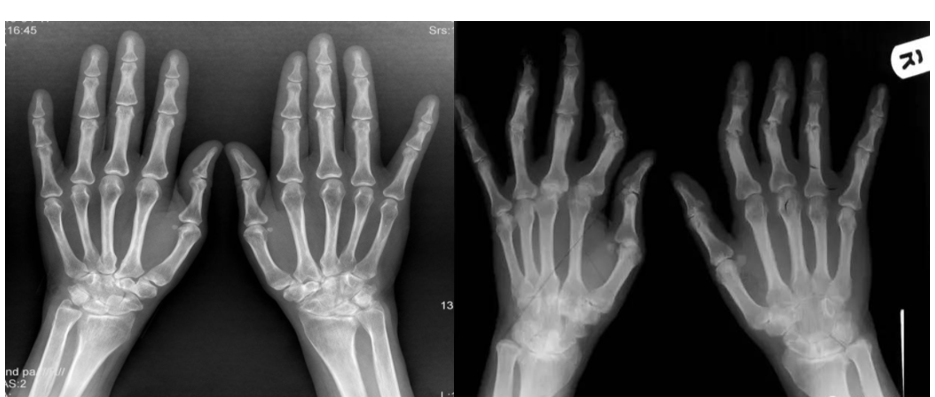

Successful demonstration of model construction

Successful model building

In order to further study rheumatoid arthritis, establishing a reliable model is the key to research. The current RA model

cannot fully reflect the clinical symptoms of human beings, and there are certain differences. Among the existing models, the collagen-

induced model and the adjuvant model are relatively It is more reliable and needs to be further explored.